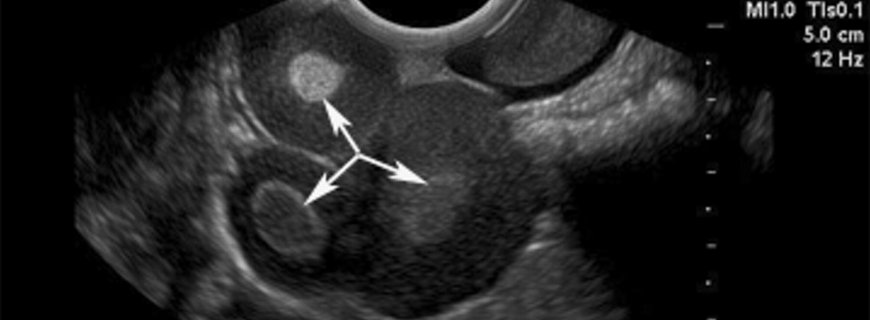

Hastalar karında ağrı veya büyüme ile başvurabilirler. X ray görüntüleme kalsiyum içeren (diş gibi) yumuşak doku kitlesini gösterebilir. Ultrasonografi, duvar komponentleri (saç, yağ), akustik gölge (kalsiyum, diş) ve yağ/sıvı seviyeleri gösteren kitleyi gösterebilir. BT görüntüleme yağ/sıvı seviyelenmesi ve kalsifikasyon/kemikleşme (diş, kemik) gösteren yumuşak dokuyu gösterebilir. MR sıvı/sıvı seviyelerini ve yağ yapılarını gösterebilir.